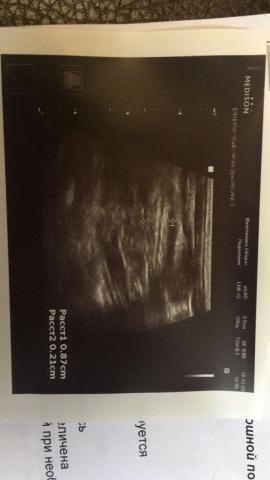

Если можно, то немного подробнее. На основании чего вам поставили такой диагноз, только на основании проведенного УЗИ? Может быть, собаке брали какие-то анализы? Если да, то выложите, пожалуйста, здесь их результаты. Если только данные УЗИ, то это разговор ни о чем (я имею ввиду панкреатит). Гастрит по данным УЗИ вообще не ставят.

Поставили диагноз на основании УЗИ , а до этого сдавали кровь

К сожалению, ничего не могу рассмотреть. Попробуйте сами прочесть описание с фото. Если сможете, сделайте снимок более качественным. Или можно снять крупнее по частям. Может быть, тогда буквы будут видны более четко.

Спасибо, фотографии четкие. Я все прочитал. Как я и думал, там и "не пахнет" никаким гастродуоденитом, а тем более, панкреатитом.